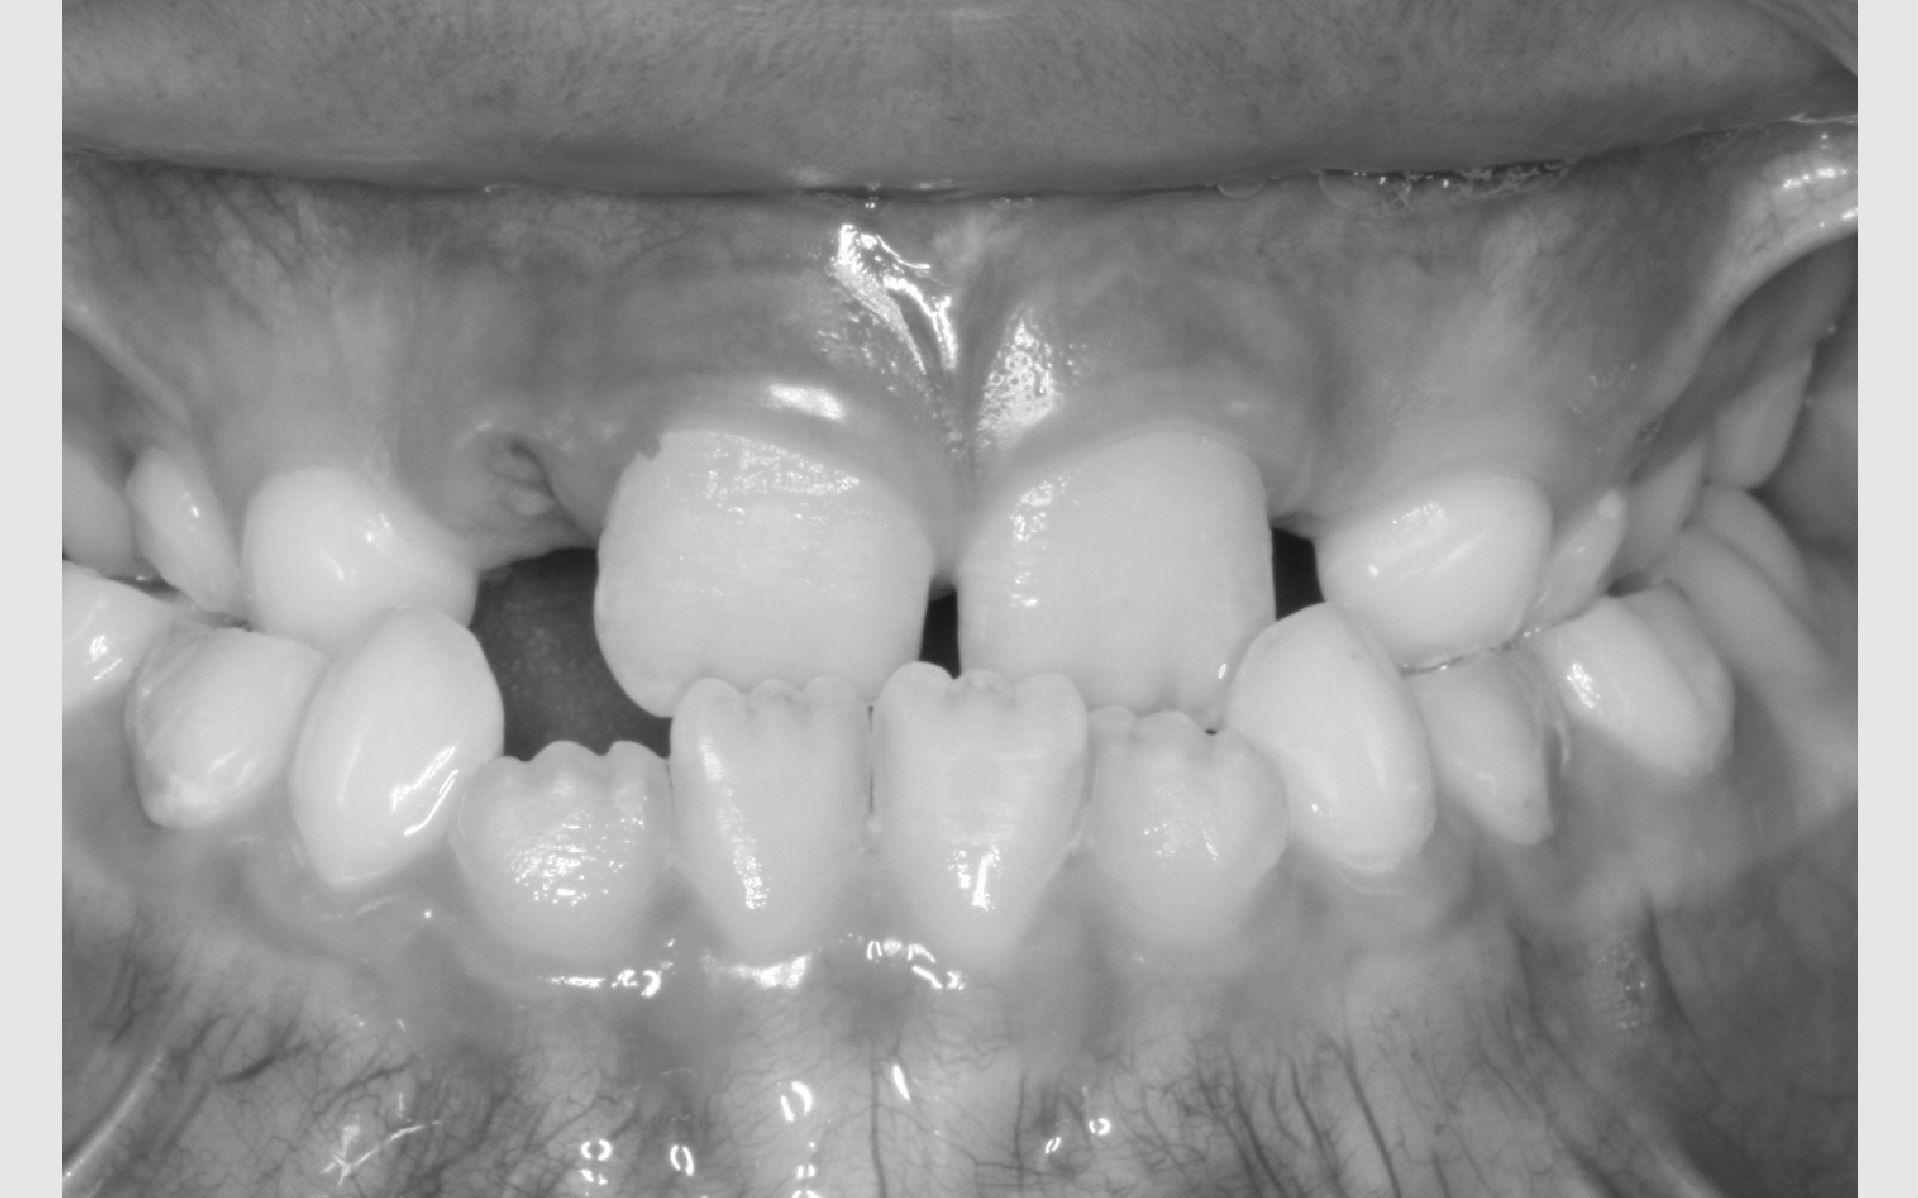

Der bliver taget billeder "udenpå og indeni" samt røntgenbilleder.

Dit barn skal selv holde sine læber til side med en læbeholder, mens tænderne bliver fotograferet. Billederne har følgende formål: